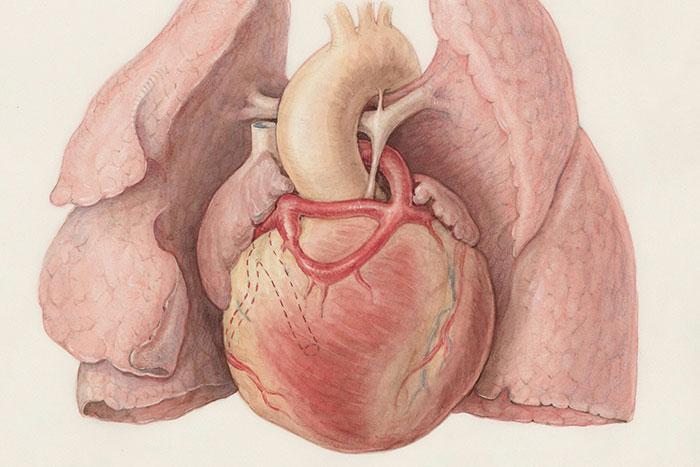

#8

The health of your teeth, or lack thereof, can cause heart disease. The bacteria that infect the gums and cause gingivitis and periodontitis also travel to blood vessels elsewhere in the body, where they cause blood vessel inflammation and damage.

If you are diabetic, and don't know it--or do, but have problems controlling your sugars, it can severely harm your teeth. On the flip side? Having bad teeth can severely affect your blood glucose as a diabetic. It can become a s****y cycle.

And yes--mentioned earlier, but if you get an infected tooth, that infection can travel to the brain or blood very fast.

And yet, teeth are still considered "luxury bones," with maintenance, cleaning, and dental care hardly ever being covered by insurance.